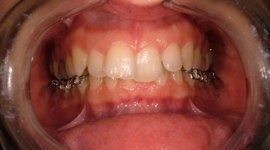

I risultati dell’ortodonzia linguale sono gli stessi di quelli ottenuti con gli apparecchi tradizionali, ma a causa della maggiore difficoltà che possono incontrare gli operatori questa tecnica è ancora usata solo da pochi specialisti in Italia e nel mondo.

I vantaggi dell’ortodonzia linguale vanno oltre l'invisibilità: consente infatti una maggiore velocità del trattamento, soprattutto nei casi con morso coperto, un minor rischio di retrazioni gengivali visibili. Garantisce un minor rischio di danni allo smalto dei denti nella superficie anteriore e una notevole efficacia nell'affrontare sintomatologie dovute a disordini e disfunzioni cranio-mandibolari.